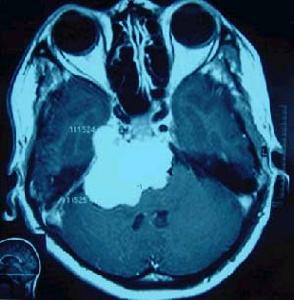

其他輔助檢查:CT或MRI可確定腦室擴大及程度及皮質萎縮的程度,有時可同時了解引起腦積水的原因。此外,CT或MRI還能了解腦積水是急性腦積水還是慢性腦積水,為臨床處理措施的套用提供依據。在腦積水的診斷中,應注意與腦萎縮引起的腦室擴大相區別,後者腦室擴大的同時可明顯地顯示出側裂或腦溝,甚至可有腦溝及腦裂的明顯擴大。另外診斷腦積水應儘可能明確是梗阻性腦積水還是交通性腦積水。

鑑別診斷:低級星形細胞瘤、腦室內囊腫,可通過MRI進行鑑別,也需要與局限性腦室擴大相鑑別。